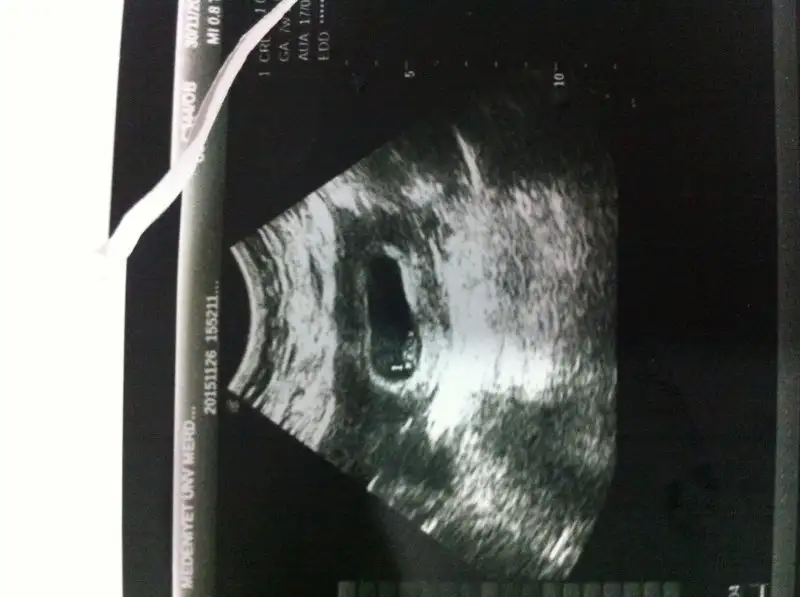

canım bu ultrason karından bahsettiğin hare sağ altta. bu durumda karından olduğu için sol sayılıyor değil mi? yani bu teoriye göre kız. başarabilirsem ultrason fotosunu atacağım canımKesenin sağda veya solda olması önemli değil canım kesenin etrafını saran hale gibi beyaz renkli alan yani plasentanın konumuna göre cinsiyet tahmini yapmışlar.

Evet canım kız oluyor ama hep 6-8 hafta arası denmiş. O tarihten sonra konum değişir mi bilmiyorum . ama bunlar eğlence. Doğrusunu Rabbim bilircanım bu ultrason karından bahsettiğin hare sağ altta. bu durumda karından olduğu için sol sayılıyor değil mi? yani bu teoriye göre kız. başarabilirsem ultrason fotosunu atacağım canım

hare sanki sol altta şayet ultrason karındansa erkek oluyor değil mi?Yüklüyorum canım sen bi incele bakalım. Benim bir kızım var 1 yaşında ikinci biraz erken oldu ama şimdi alıştım. Tabi ki bu cinsiyet tahminlerine inanmıyorum. Tutsada denk geldiğinden.

Ultrason karından bu benim ilk randevumdu. Bi daha da gitmedim. 1 ay sonra tekrar gidip karşılaştırmak istiyorumhare sanki sol altta şayet ultrason karındansa erkek oluyor değil mi?

Buna gore erkek olmasi gerek :)Görüntülerin ikisi de karından bakılan foto sizce benim bebeğim cinsiyeti nedir